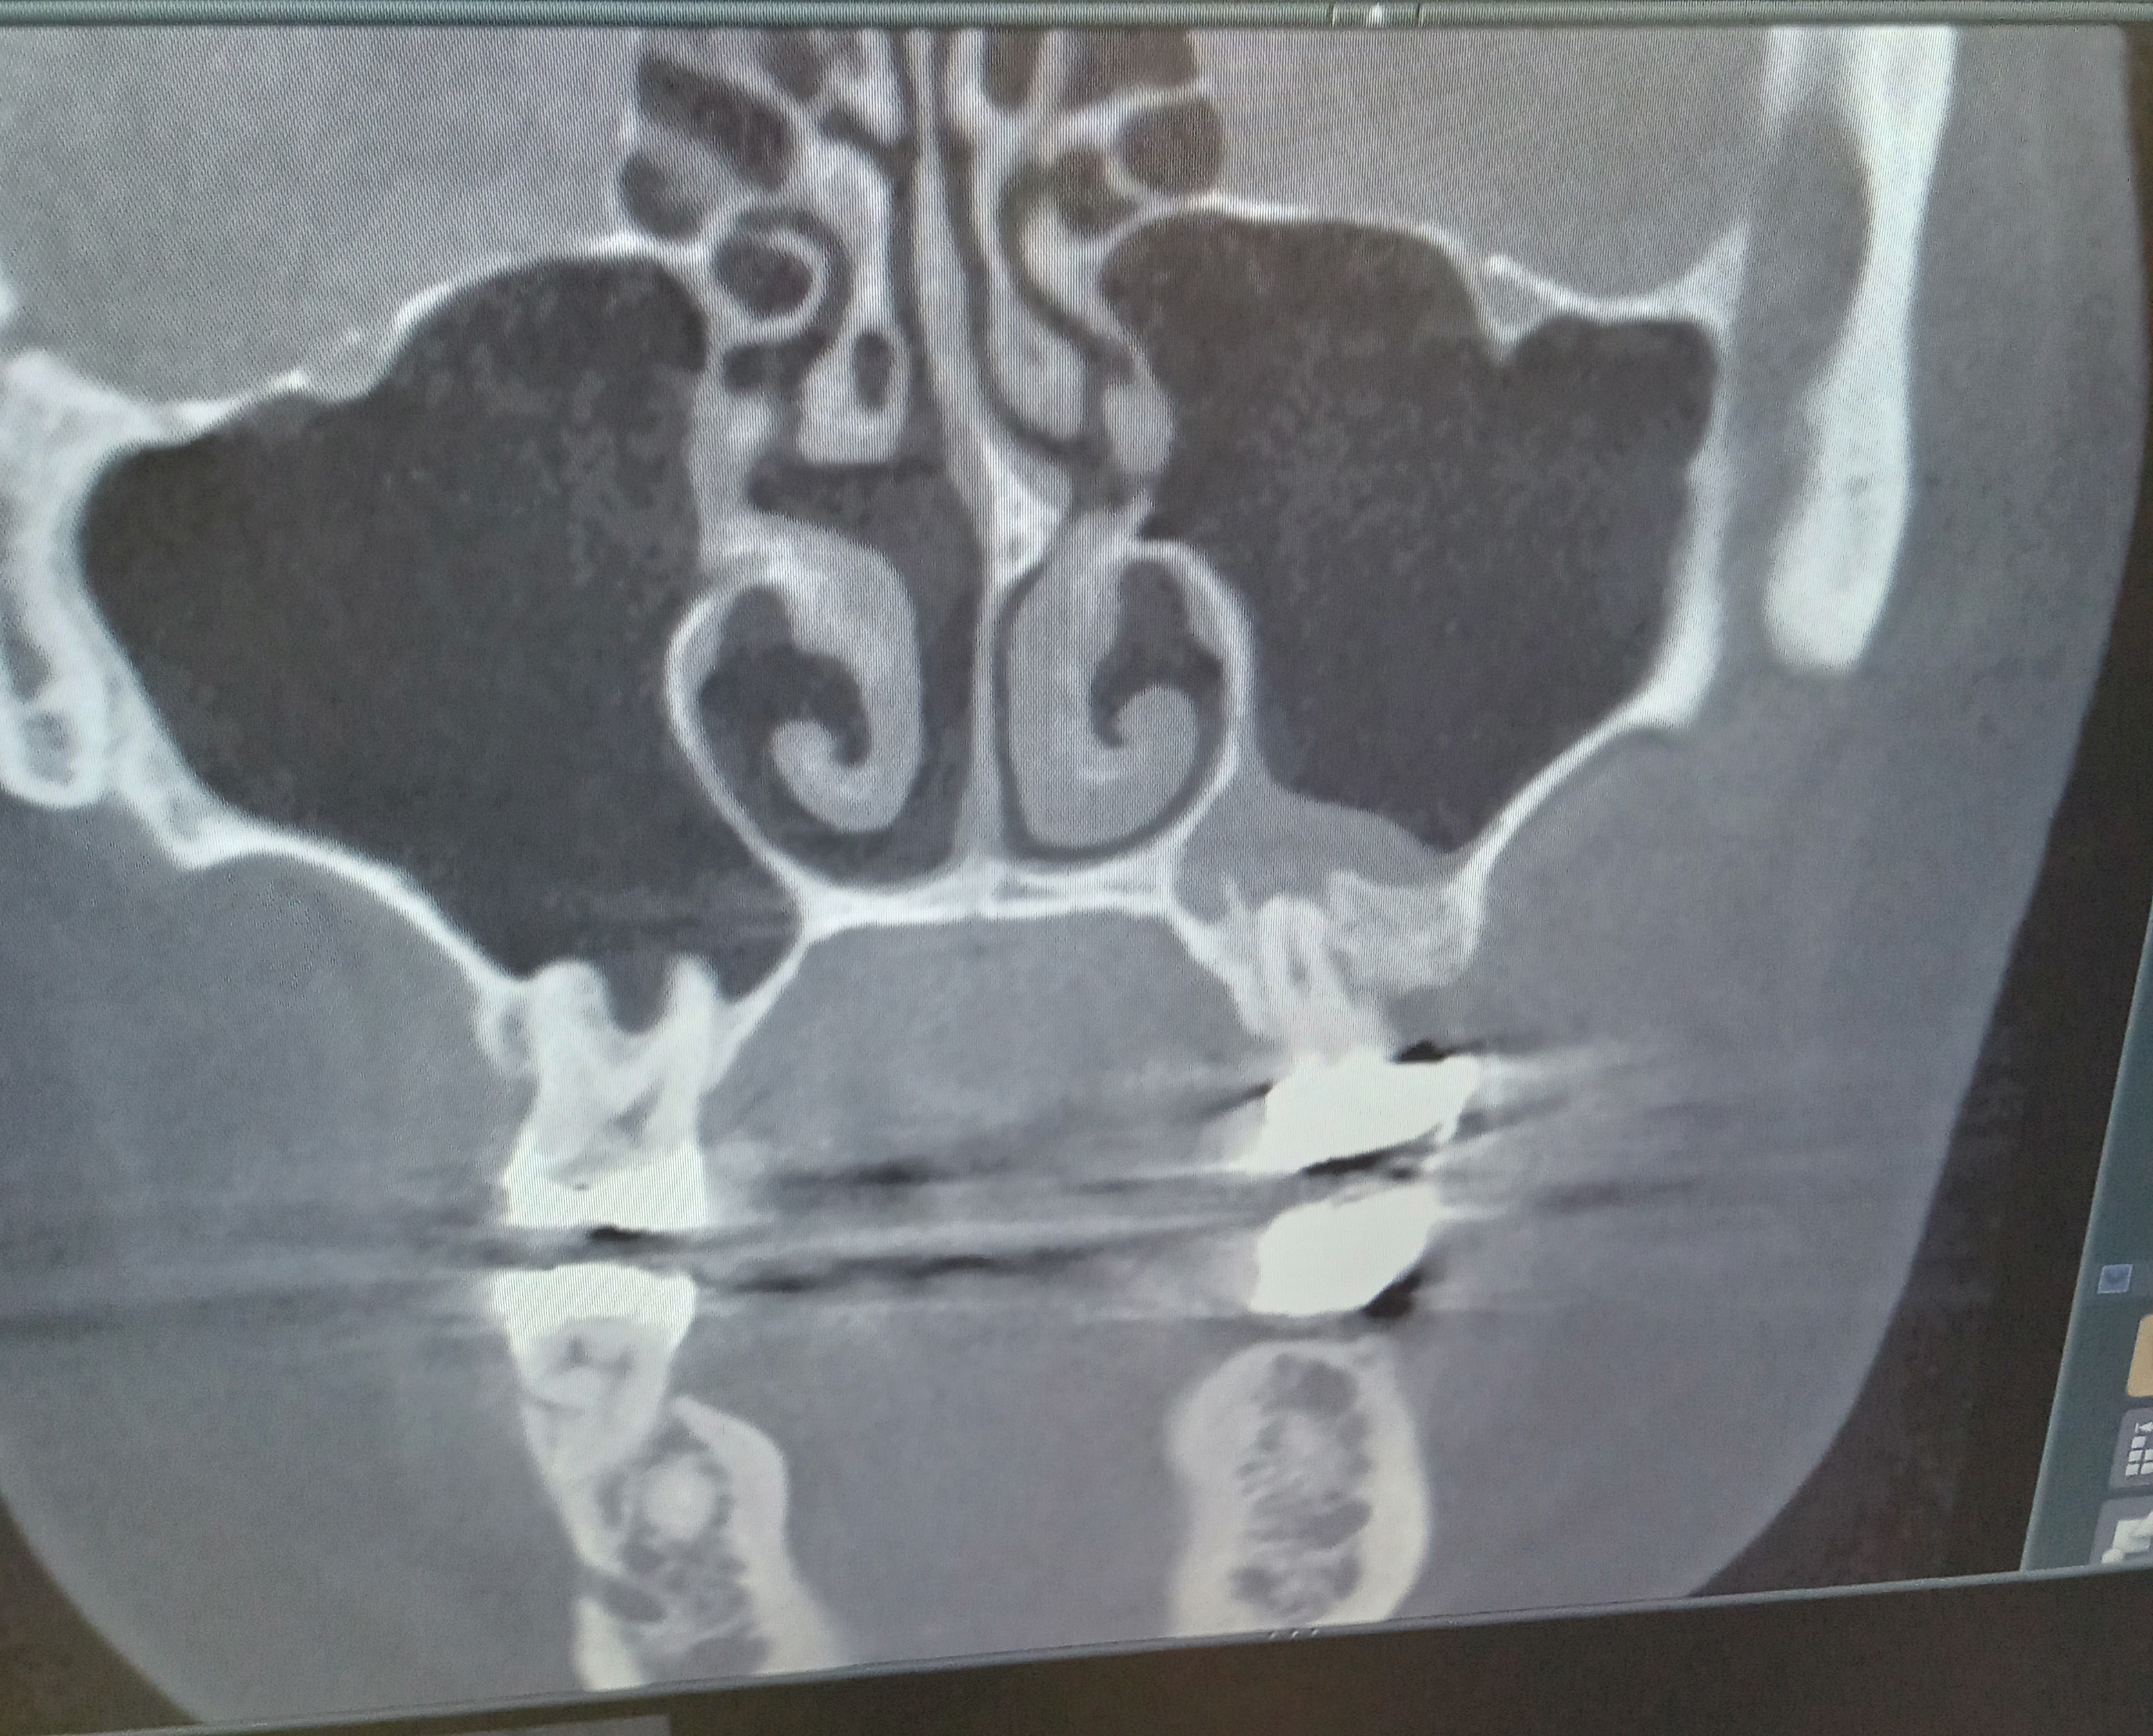

歯性上顎洞炎になっていると言われました。根管治療で歯を残せますか?